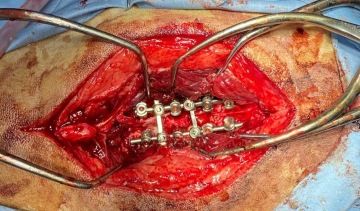

Veterinární chirurgové se učí od chirurgů lidských. Postupy aplikované na humánního pacienta se adaptují na pacienta zvířecího. Veterinární neurochirurgové umí odstranit nádor z mozku, operovat vyhřezlý meziobratlový disk, stabilizovat nestabilní páteř pomocí 3D tištěných operačních šablon.

Lumbosakrální spinální stabilizace

Jedny z nejnáročnějších operací jsou zákroky na deformované páteři francouzských buldočků a mopsů. Vyžadují předchozí CT a MRI vyšetření, speciální 3D tištěné vrtací šablony pro bezpečné usazení implantátů a v zásadě vytvoření nové podpůrné páteře z polymetylakrylátu (kostní cement). Takové zákroky trvají i několik hodin a vyžadují extenzivní plánování a maximální soustředění celého operačního týmu během celého zákroku.

Asi si dokážete představit úlevu, když se váš pacient po takovém zákroku postaví a udělá první vrávoravé kroky.

Fotky z operací

(není pro citlivé povahy:)